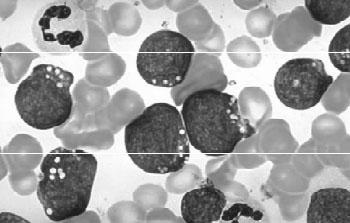

(7)急性巨核细胞白血病(M7):外周血中有原始巨核(小巨核)细胞;骨髓中原始巨核细胞≥30%;原始巨核细胞有电镜或单克隆抗体证实;骨髓细胞少,往往干抽,活检有原始和巨核细胞增多,网状纤维增加。AML各亚型常和免疫表型、染色体异常及相应的融合基因有对应关系(见图3—11)。

图3—11 AML—M7骨髓象